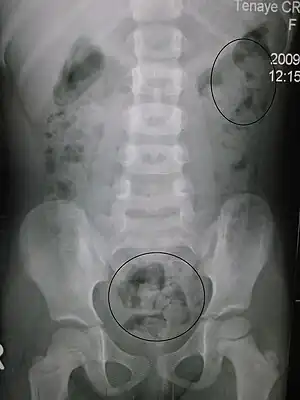

Abdominal x-ray

An abdominal x-ray is an x-ray of the abdomen. It is sometimes abbreviated to AXR, or KUB (for kidneys, ureters, and urinary bladder).

KUB is typically used to investigate gastrointestinal conditions such as a bowel obstruction and gallstones, and can detect the presence of kidney stones. The KUB is often used to diagnose constipation as stool can be seen readily. The KUB is also used to assess positioning of indwelling devices such as ureteric stents and nasogastric tubes. KUB is also done as a scout film for other procedures such as barium enemas.